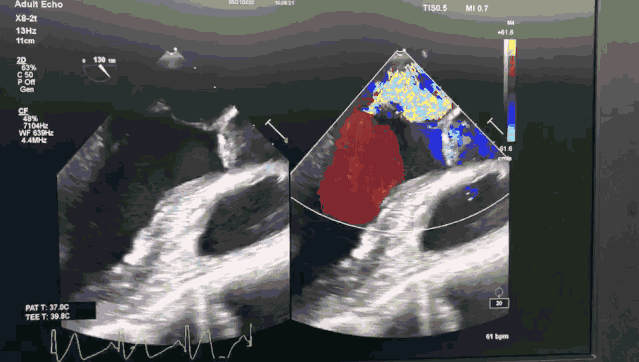

患者是71岁老年男性,体格消瘦,极重度二尖瓣反流,后叶P2及部分P3脱垂,同时合并重度肺动脉高压,STS评分6.1%,外科手术风险高。

今日手术转播的导管操作时间仅用8分钟,一次性成功。患者术后即刻效果满意,二尖瓣反流从极重度减少到轻中度,未出现二尖瓣狭窄,肺动脉高压从重度降为正常,手术效果良好。

图1 ValveClamp术前经食道心超

图2 ValveClamp术后经食道心超